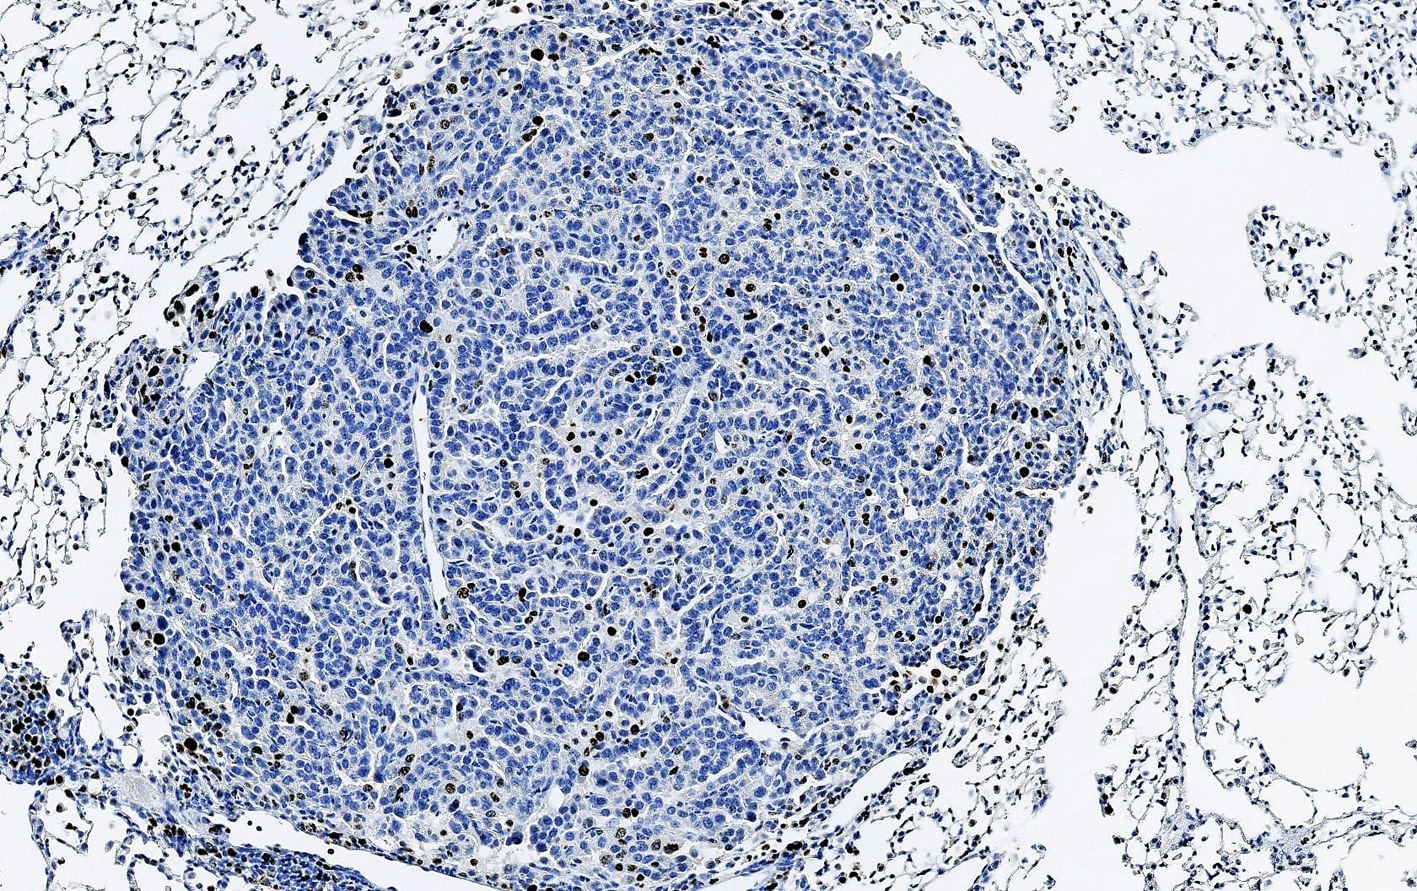

Vista microscópica del cáncer de pulmón (IRB)

Vista microscópica del cáncer de pulmón (IRB)Las alteraciones en el EGFR son mutaciones genéticas frecuentes en el cáncer de pulmón de células no pequeñas y, específicamente, las alteraciones en las inserciones del exón 20 del EGFR son las terceras mutaciones primarias del EGFR más prevalentes, representando hasta el 10% de estas.